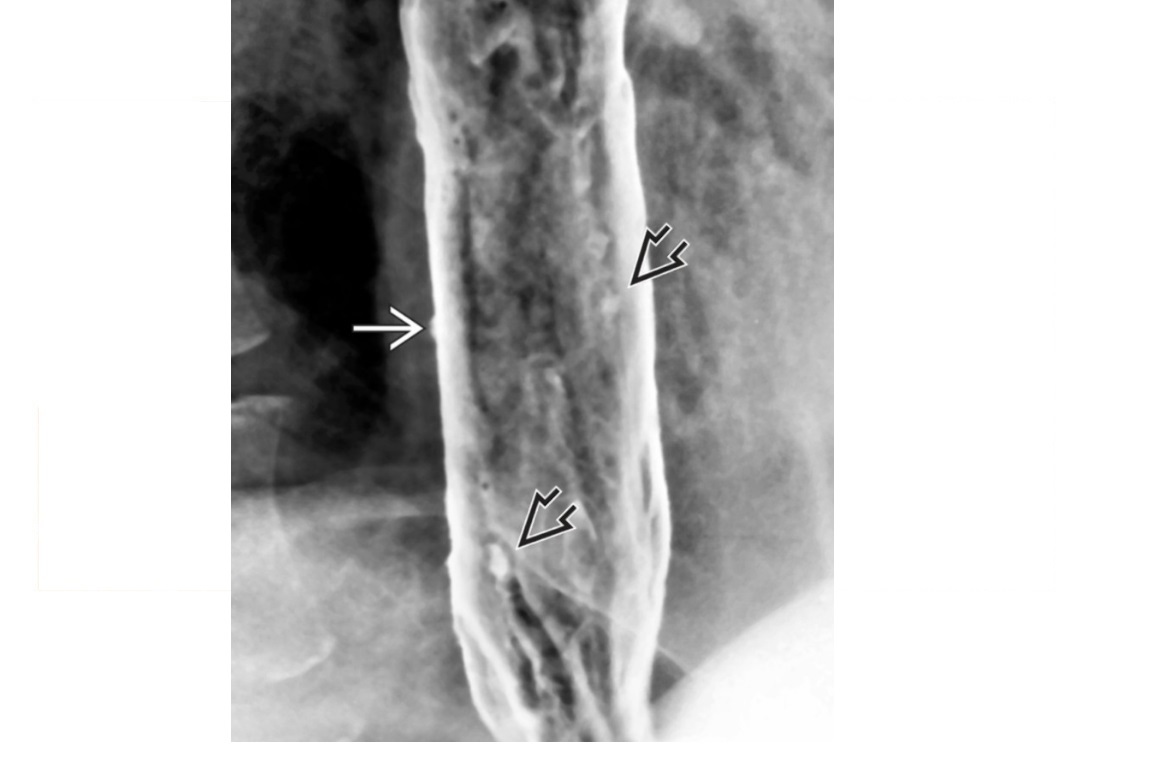

Caustic

long stricture ± diffuse ulceration of lower and mid oesophagus

Stomach can be pulled into the chest as the oesophagus shortens and strictures

DDX Long stricture

-NG tube in too long or radiation - These are usually smooth